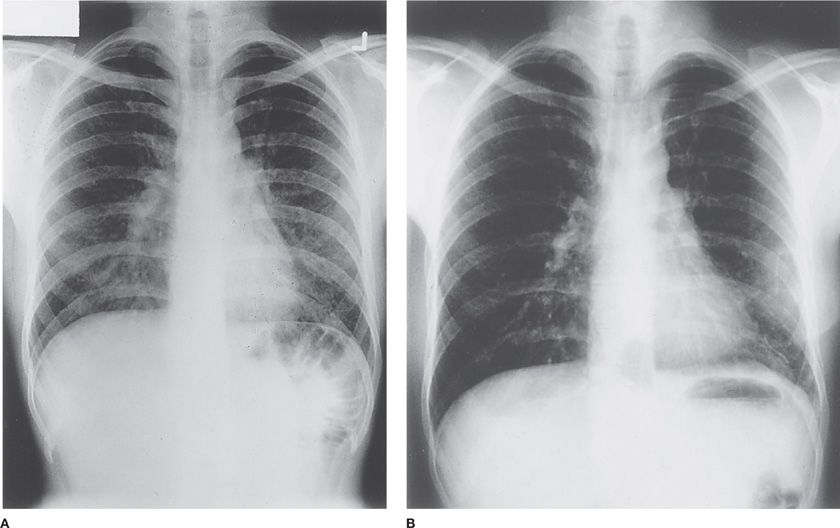

Pigeon Chest X Ray Pigeon Chest Causes And Symptoms pectus carinatum is a condition in which your sternum (breastbone) sticks out more than usual. Pectus carinatum, sometimes called pigeon. Pectus carinatum is a condition that causes the chest to a have a “bowed out” or “pigeon chest”. Some people call it “pigeon. pectus carinatum (pigeon chest) refers to a chest wall deformity in which the sternum protrudes. Pigeon Chest Causes And Symptoms.

Hypersensitivity Pneumonitis Thoracic Key Pigeon Chest Causes And Symptoms It is less common than pectus excavatum. Some people call it “pigeon. what is pectus carinatum. Pectus carinatum occurs when the cartilage, the bones of the. this page explains the common causes, symptoms, diagnosis and treatment of pectus carinatum (pigeon chest). pectus carinatum (pigeon chest) refers to a chest wall deformity in which the sternum protrudes anteriorly.. Pigeon Chest Causes And Symptoms.